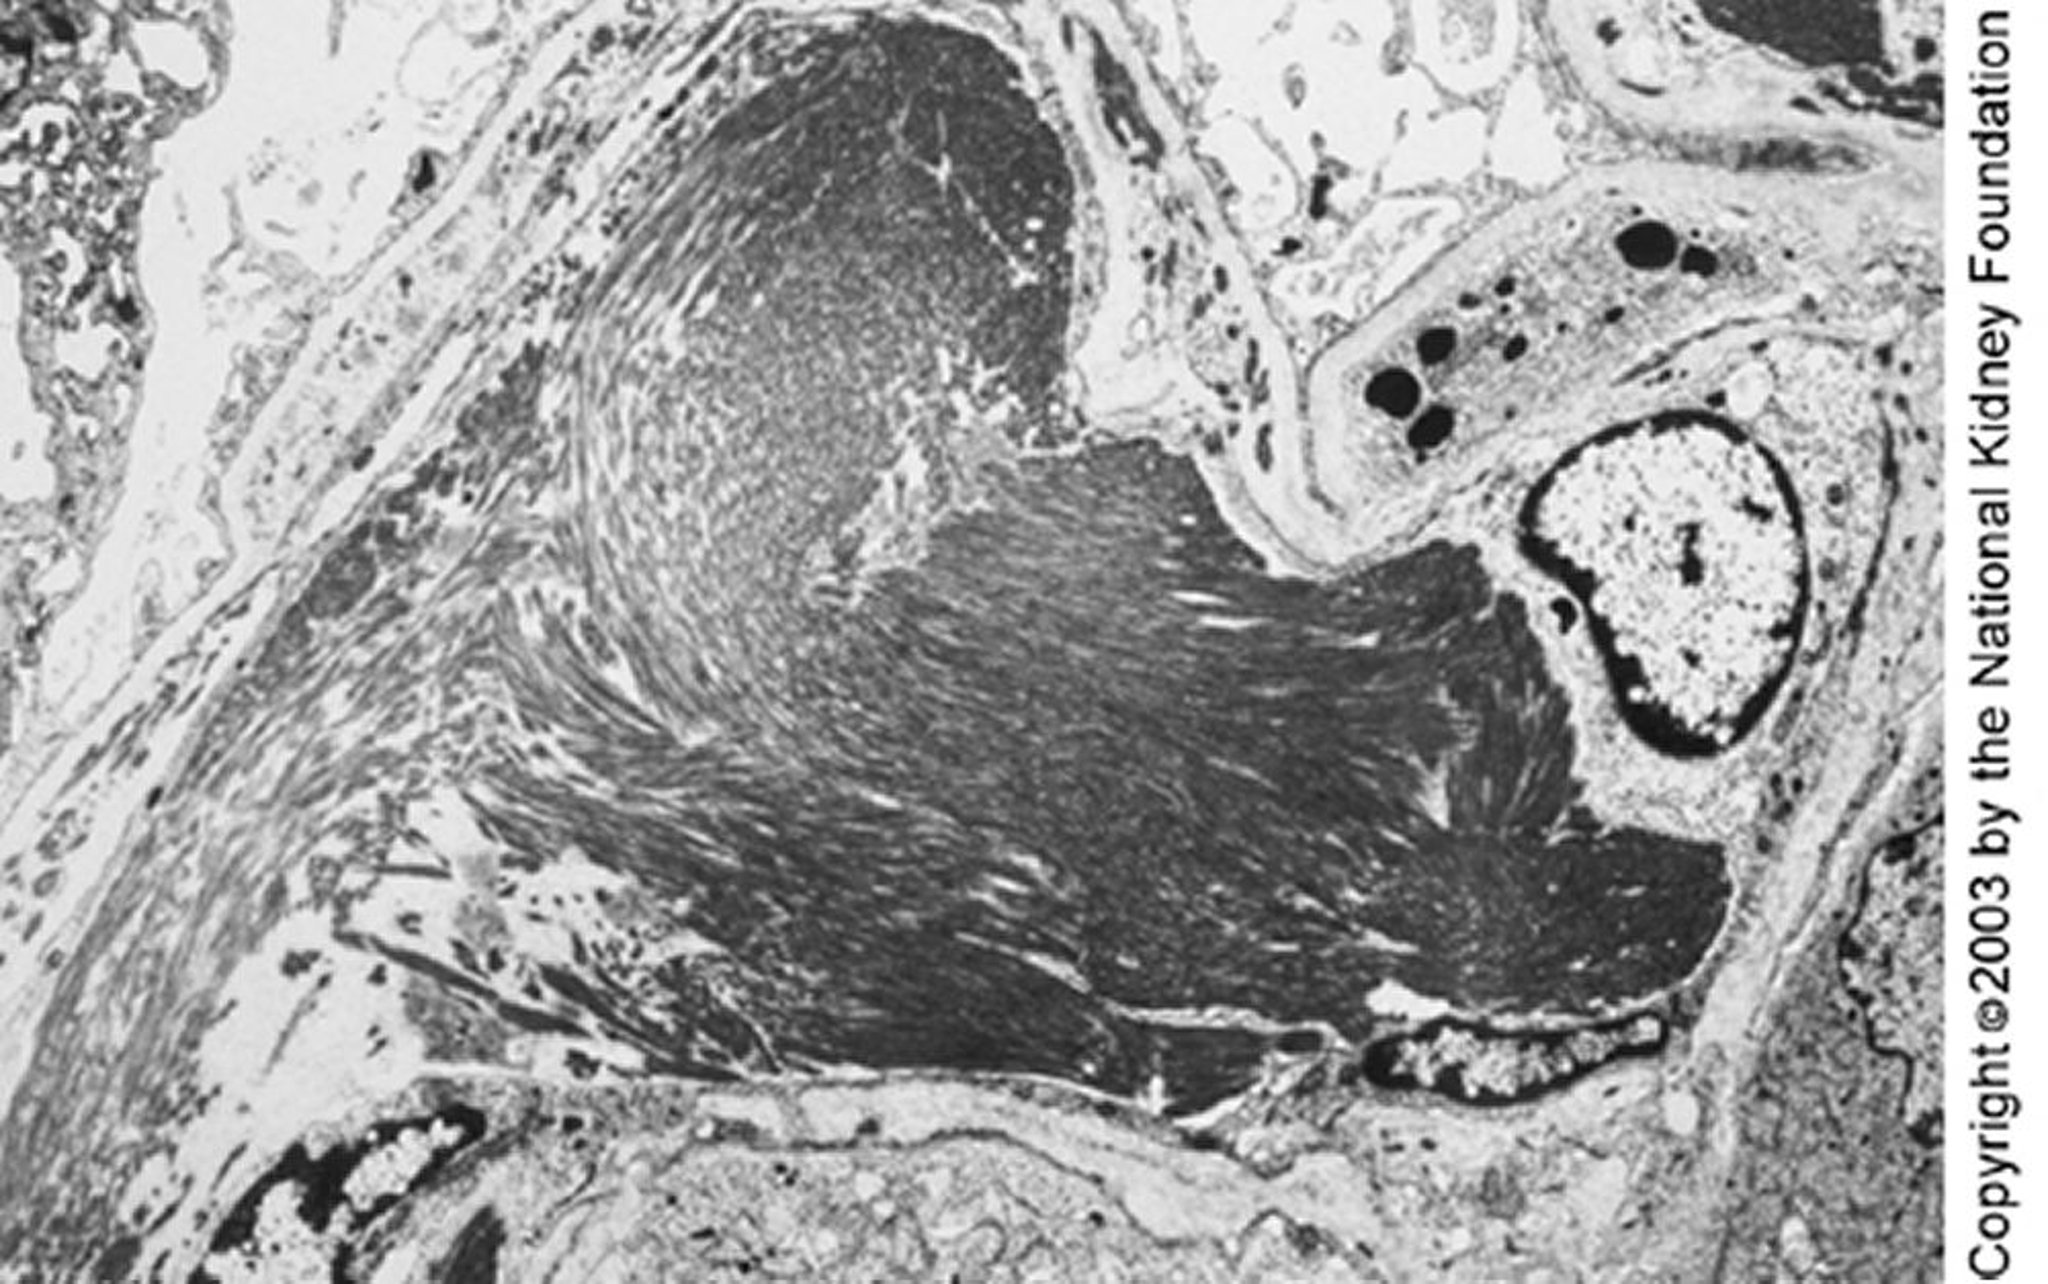

De grands microtubules (de près de 50 nm de diamètre) organisés en réseaux parallèles peuvent être vus en microscopie électronique à transmission. Les dépôts parallèles et la structure microtubulaire peuvent permettre de distinguer la glomérulopathie immunotactoïde de la glomérulopathie fibrillaire (×4000).

Image fournie par Agnes Fogo, MD, and the American Journal of Kidney Diseases' Atlas of Renal Pathology (voir www.ajkd.org).